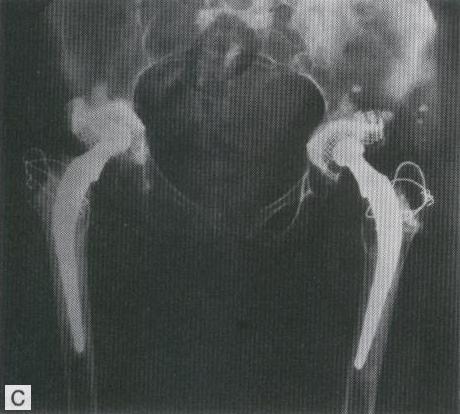

COLOCACION DE PROTESIS TOTAL BILATERAL